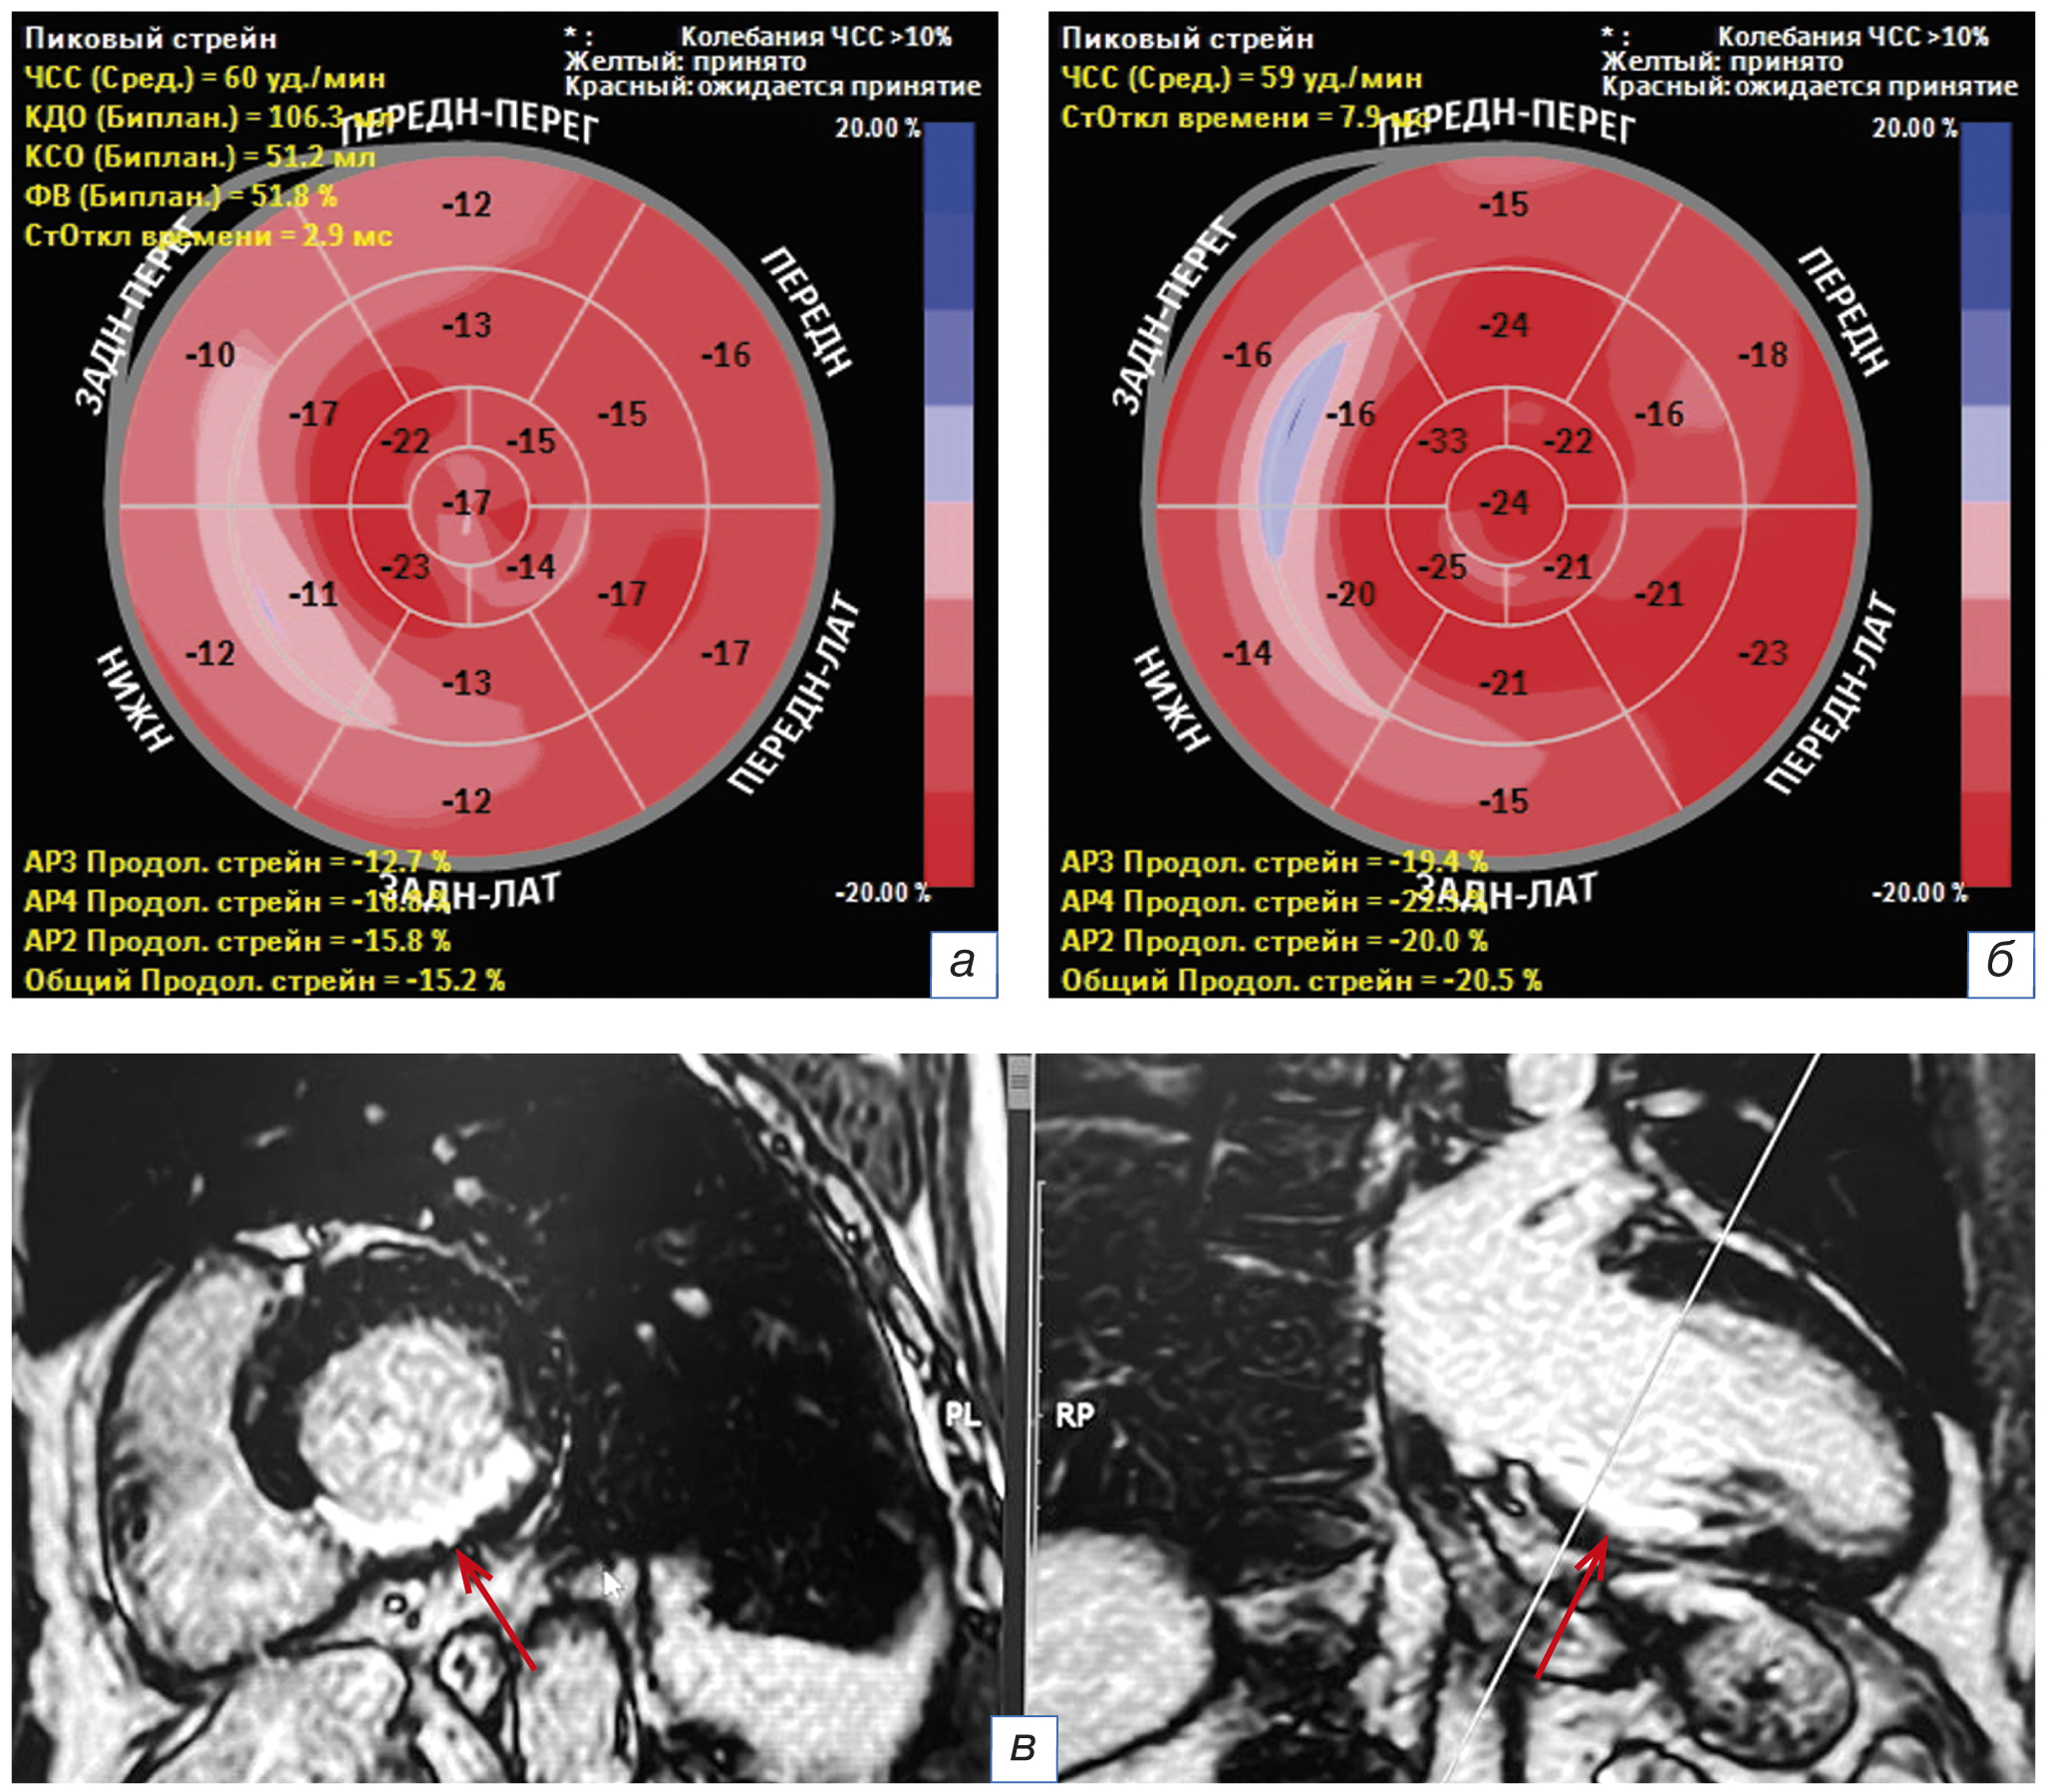

Степень систолической деформации миокарда по спекл-трекинг эхокардиографии в сегментах с фиброзными изменениями по МРТ была статистически значимо меньше, чем в неизменённых сегментах (табл. 2; рис. 2). Диагностическая информативность ультразвуковых значений относительно данных МРТ по чувствительности (46–57%), специфичности (68–76%) и отрицательной предсказательной ценности (74–87%) определилась значимой для прогнозирования фиброза в постинфарктный период. Низкая положительная предсказательная ценность 38–46% сегментарной деформации ЛЖ свидетельствует о большой доле ложноположительных значений. Взаимосвязь между количеством фиброзных сегментов по МРТ и глобальными деформациями по эхокардиографии отсутствовала.

Рис. 2. Пациент с фиброзными изменениями нижней стенки левого желудочка после острого инфаркта миокарда: а — «бычий глаз» с сегментарной продольной деформацией левого желудочка на 5-й день острого инфаркта миокарда нижней стенки левого желудочка; б — «бычий глаз» с сегментарной продольной деформацией левого желудочка через 17 месяцев; в — изображение магнитно-резонансной томограммы по короткой (слева) и длинной (справа) оси через 17 месяцев после острого инфаркта миокарда (стрелки). ЧСС — частота сердечных сокращений; КДО/КСО — конечный диастолический/систолический объём; ФВ — фракция выброса.

Fig. 2. A patient with fibrotic changes in the lower wall of the left ventricle after acute myocardial infarction: а — «bull’s eye» with segmental longitudinal deformation of the left ventricle on the 5th day of acute myocardial infarction of the lower wall of the left ventricle, б — «bull’s eye» with segmental longitudinal deformation of the left ventricle after 17 months, в — magnetic resonance tomogram image in short (on the left) and long (on the right) axis 17 months after acute myocardial infarction (arrows). ЧСС — heart rate; КДО/КСО — end-diastolic/systolic volume; ФВ — ejection fraction.